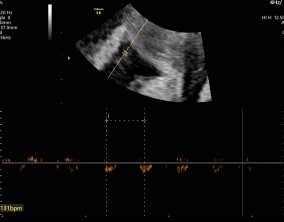

임신 수치 16, 9주차 기적의 기록

서울IVF에서는 단순히 배아 생성과 이식만 해주시는 것이 아니라, 제 생활 전반까지 신경 써주셨습니다. 휴식기에도 그저 기다리는 것이 아니라 항노화에 도움이 되는 링겔을 처방…